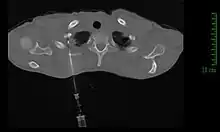

Modalités diagnotiques

Si la clinique et l'imagerie permettent à elles seules de poser le diagnostic de tumeur de Pancoast-Tobias, ce n'est que l'analyse d'une biopsie tissulaire qui permettra d'identifier le type de tumeur, et ainsi de guider le traitement[11].

La méthode de diagnostic la plus précise est la ponction percutanée trans-thoracique par ponction à l’aiguille, sous contrôle scanner, qui présente un rendement de 95 %[11],[21]. En cas d'échec, il est possible de réaliser une biopsie chirurgicale par thoracoscopie ou thoracotomie[11].